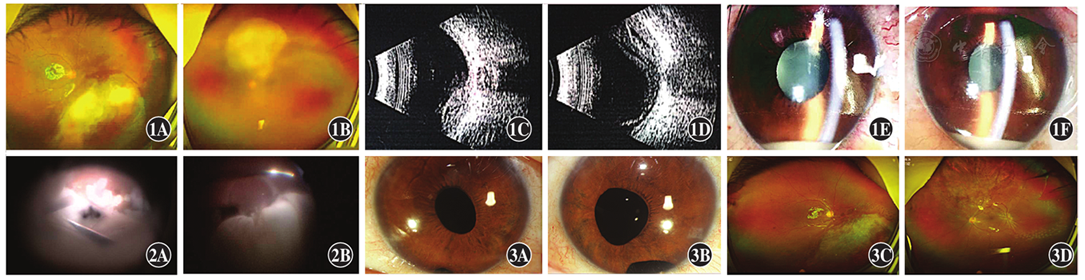

患者,男,40岁,2018年2月8日因发热伴肌肉酸痛4 d于扬州大学附属苏北人民医院肝胆内科就诊。患者否认高血压、糖尿病史;体温39.6 ℃,随机血糖水平为21.9 mmol/L,糖化血红蛋白水平为13.3%;上腹部增强CT检查显示肝左叶低密度影,考虑肝脓肿可能;胸部CT平扫结果显示双肺下叶炎症,以"肝脓肿、肺炎、2型糖尿病"收入院。在B型超声引导下行肝脓肿穿刺引流术,穿刺液细菌培养提示肺炎克雷伯菌阳性。根据药物敏感性试验结果予以比阿培南0.3 g静脉滴注,每日3次,并采用降血糖等对症治疗,全身情况好转。2018年2月11日因左眼进行性视物模糊2 d、右眼视物模糊1 d请眼科急会诊。患者否认眼部手术及外伤史。右眼视力数指/眼前,裂隙灯显微镜检查下可见结膜充血,角膜透明,房水混浊,瞳孔直径3 mm,对光反射存在,晶状体尚透明,玻璃体腔絮状混浊,扩瞳检查眼底见下方视网膜大片黄白色病灶(图1A);左眼视力光感,结膜充血水肿,角膜轻度水肿,前房积脓2~3 mm,虹膜后粘连,瞳孔欠圆,对光反射消失,晶状体尚透明,玻璃体混浊,扩瞳检查眼底见视盘上方黄白色病灶(图1B)。双眼眼压正常。眼部B型超声检查示双眼玻璃体混浊,右眼视网膜向玻璃体腔内隆起(图1C),左眼视网膜脱离(图1D)。诊断:双眼内源性眼内炎。患者要求转上级医院,但因故于次日再次入院。患者诉右眼视物模糊加重,视力光感,前房积脓(图1E),液平略高于左眼(图1F),玻璃体混浊加重。患者空腹血糖水平为8.2 mmol/L,体温36.9 ℃。于2018年2月13日和14日于全身麻醉下分别行右眼、左眼23G后入路玻璃体切割+晶状体超声乳化+硅油注入+双眼玻璃体腔注药术(10 g/L万古霉素0.1 ml+20 g/L头孢他啶0.1 ml)。左眼术中见视网膜下大量黄白色脓苔样物质,切开视网膜后尽量清除(图2)。双眼玻璃体标本液细菌及真菌培养结果均为阴性。术后第2天右眼前房再次积脓,行上述抗生素右眼玻璃体腔注射,降血糖及全身控制感染用药方案同术前,患者血糖及体温均稳定。患者2018年3月5日出院,双眼裸眼视力数指/50 cm,角膜透明,前房清(图3A,B),晶状体及囊膜缺如,玻璃体腔硅油填充,视网膜平伏,可见散在激光斑(图3C,D)。后因增生性玻璃体视网膜病变伴视网膜脱离,于2019年6月12日和2019年7月31日分别行右眼和左眼玻璃体腔硅油置换术。患者出院后定期门诊复查,2019年10月10日复查最佳矫正视力右眼0.1,左眼0.2,目前仍在随访中。